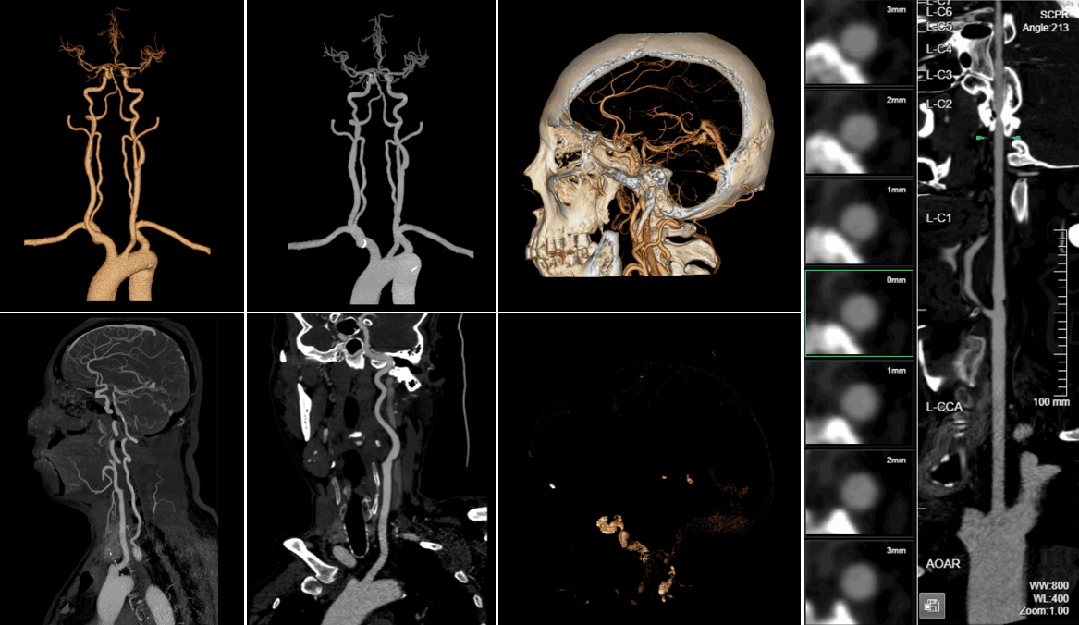

该产品于2023年9月进入国家创新医疗器械特别审查通道。该产品由软件安装程序和授权文件组成,功能模块包括浏览器端、服务器端,用于头颈动脉CT血管造影图像的显示、处理、测量和分析,可对颅内3mm及以上动脉瘤进行辅助检测。该产品采用基于深度学习的头颈血管分割分段技术和多尺度动脉瘤检测技术,有效提高了颅内动脉瘤的诊断准确性和效率,对提升患者生存率具有重要意义。